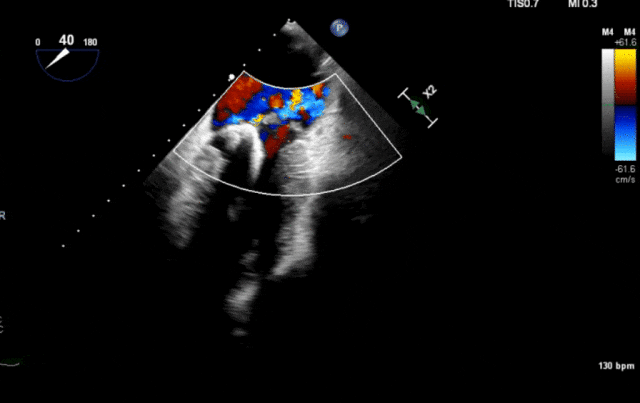

心脏超声示左室增大,二尖瓣2、3区脱垂伴重度反流(腱索断裂),Carpentier分型Ⅱ型,典型Barlow综合征表现;二尖瓣开放面积5.0cm²,3区瓣环内径31mm,前叶长22mm、后叶17mm,前叶收缩期关闭瓣体部分呈拱形突向左房腔,瓣膜游离缘对合欠佳,可见腱索断裂,长度9mm;2区瓣环内径32mm,前叶长22mm、后叶10mm,前后叶均可脱垂;三尖瓣重度反流。CDFI示瓣口重度偏心性反流,反流束沿主动脉后壁走行,肺静脉收缩期可见反向频谱。

术前反流

图片